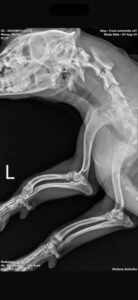

His left front paw turns out a little more sideways than the other one. He’s had X-rays and all is in order, no accident or injury, he was born like this. It doesn’t bother him as he loves to go for walks, run and play.